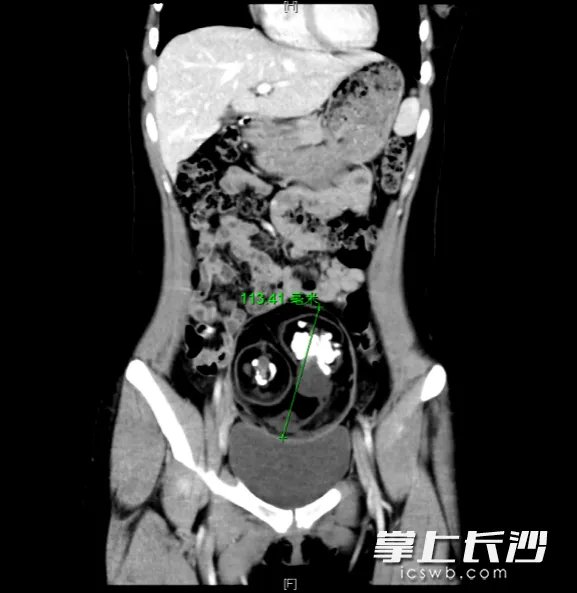

CT检查显示,患者下腹部有一直径约12厘米的肿块。均为通讯员供图

长沙18岁的琳琳(化名),近日在家跳操时突然出现右下腹持续性剧烈疼痛,立即前往长沙市中心医院(南华大学附属长沙中心医院)妇科就诊。彩超检查报告显示,她的下腹部藏着一个直径约12厘米的巨大肿块,更令人惊讶的是,肿块内部疑似有牙齿和骨骼的影像体现。